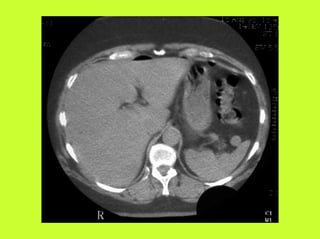

3) RADIO (PNO)

RADIOGRAPHIES

ABDOMEN SP -scanner

AUTRES EXAMENS

"TOGD aux hydrosolubles?

" Echo, scanner

" Coelioscopie ?

RADIOGRAPHIES ABDOMEN SP -scanner PNEUMOPERITOINE SUR SUJET DEBOUT " Croissant gazeux sous diaphragmatique " Disparition du niveau hydroaérique gastrique PNEUMOPERITOINE SUR SUJET COUCHE " Visibilité du ligament triangulaire du foie " Visibilité anormale des parois intestinales " Image aérique pré-hépatique "Pneumatisation de MORRISSON (cul de sac inter-hépato-rénal) AUTRES EXAMENS "TOGD aux hydrosolubles? " Echo, scanner " Coelioscopie ? " Pas de lavement colique, pas de fibroscppie, pas de coloscopie, pas d’IRM